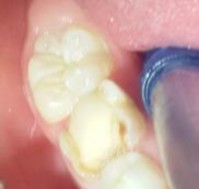

Hình 2.12: Phủ một lớp mỏng vật liệu lên mặt răng | |

Hình 2.13: Chiếu đến 20s | Hình 2.14: Mặt răng sau điều trị |